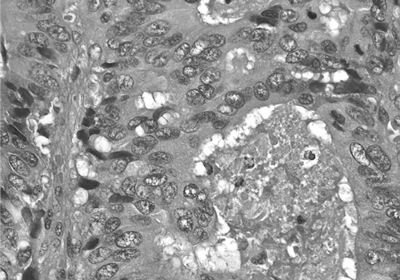

8.病理医による診断(1日)

出来上がった組織標本を、病理医が顕微鏡により診断をします。必要があれば、さらに追加の切り出しを行って確認したり、特殊な染色を行ったりすることもあります。難解症例では、大学などの専門機関に相談したりします。

診断は、病理所見とともに報告書としてまとめられ、主治医に伝えられます。

大腸癌の顕微鏡像